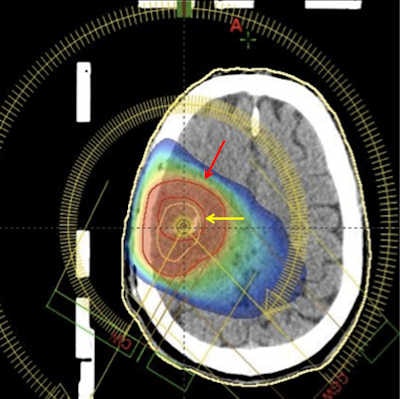

One of the best ways to attract young people to a research field is to make its characteristics visible and underline its strength in improving healthcare. Recent developments in molecular imaging fit well with this goal. Besides FDG-PET, more advanced techniques are entering the clinical arena. Evaluation of response in lymphoma and solid tumors, along with the integration of PET images in radiation therapy planning, are just a couple of strong examples of new applications of FDG PET/CT in oncology. Infection imaging is another emerging field, and improvements are being made in diagnosing infectious diseases, in which other imaging techniques have been of little value.

The real frontier is the introduction of new radiopharmaceuticals in clinical practice. New and specific probes are already available in academic centers: choline for prostate cancer and primary liver carcinoma, methionine for brain tumors, somatostatin analogue peptides for neuroendocrine tumors, fluoride for bone imaging, and fluorothymidine for cell proliferation. These are just some examples of the great potential of PET/CT imaging in oncology using radiopharmaceuticals. New radiopharmaceuticals are already in the pipeline and are going to be able to characterize certain aspects of different tumors, allowing the treatment to be tailored to the individual patient.